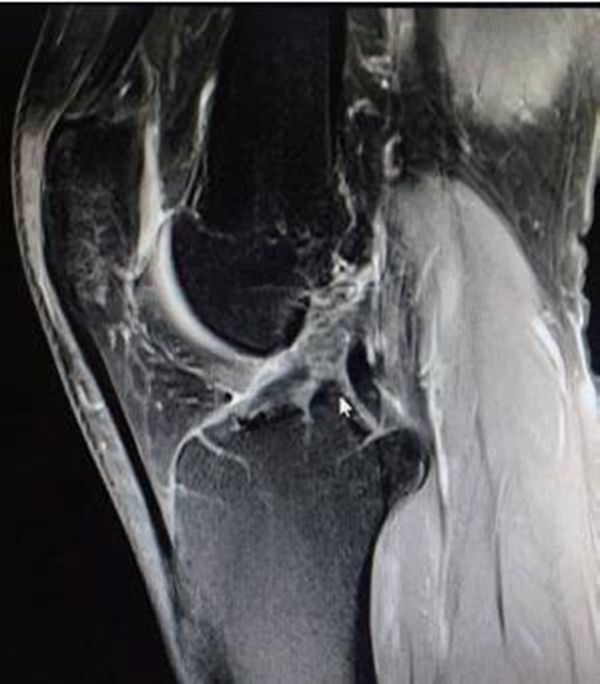

MRI检查不可作为ACL断裂的唯一诊断标准,临床上有部分ACL断裂后残端移位不明显,而是以瘢痕黏附于PCL或股骨髁的内侧面(图9)。该类情况需要临床医生对正常ACL的影像有清晰的认识,可以通过冠状位和矢状位上ACL的方向和角度来辨别,更重要的是与临床体格检查及病史三者结合以诊断。

图9 ACL断裂后断端移位不明显的MRI影像